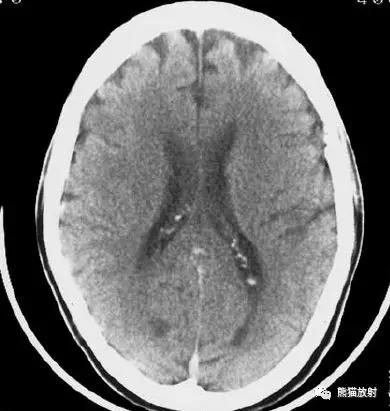

右侧豆状核梗死灶(发病后15d),明显均匀强化。另左侧丘脑见腔隙性梗死灶。

左侧大脑中动脉区域大面积梗死,明显不均质强化。

右侧大脑中动脉区域脑梗死,脑回样强化。

左侧额叶脑梗死(发病后12d),由于模糊效应平扫显示不清,增强扫描脑回样强化。

右侧基底节区脑梗死,增强后病灶看上去有所缩小。